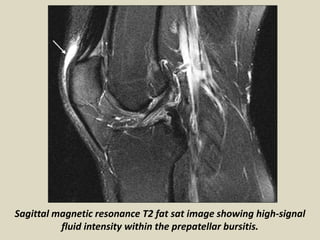

Sagittal magnetic resonance T2 fat sat image showing high-signal

fluid intensity within the prepatellar bursitis.

Sagittal magnetic resonanceT2 fat sat image showing high-signal fluid intensity within the prepatellar bursitis.